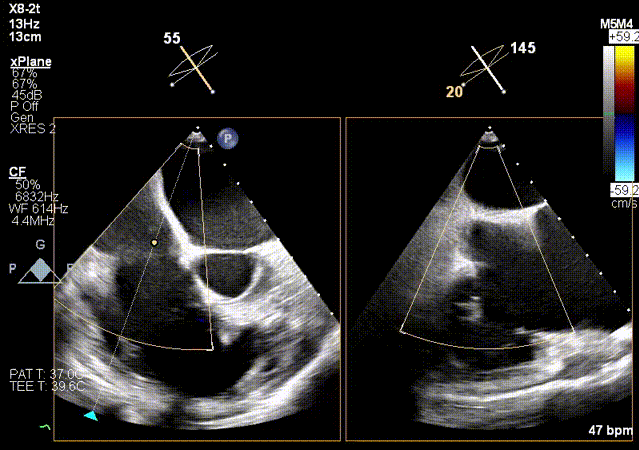

2.超声X-Plane以及实时3D下观察输送系统头端指向目标靶位。

X-Plane

3.超声MPR模式下攻入锚定部件。

MPR下攻入锚定部件